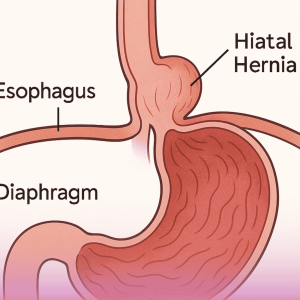

Hiatal Hernia Repair surgery

A hiatal hernia is a condition that occurs when part of the stomach pushes into the chest cavity through an abnormal or enlarged opening in the diaphragm, the muscle that separates the chest from the abdomen. Hiatal hernias are often accompanied by symptoms of gastroesophageal reflux disease (GERD).